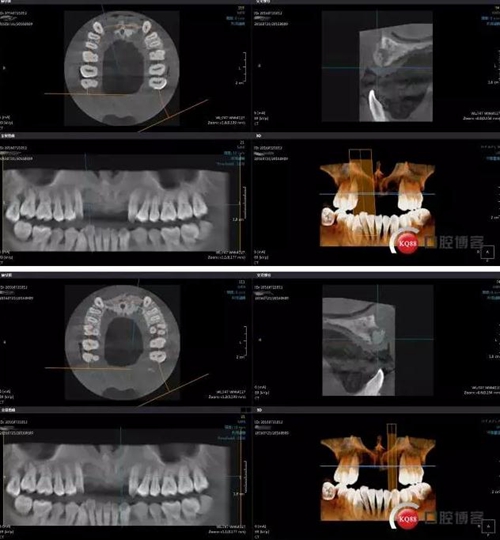

接下來是GBR五個月后CBCT,當(dāng)然(1-5月)中間也有拍全景,不一一展示了。

成骨效果尚可,進(jìn)行手術(shù)